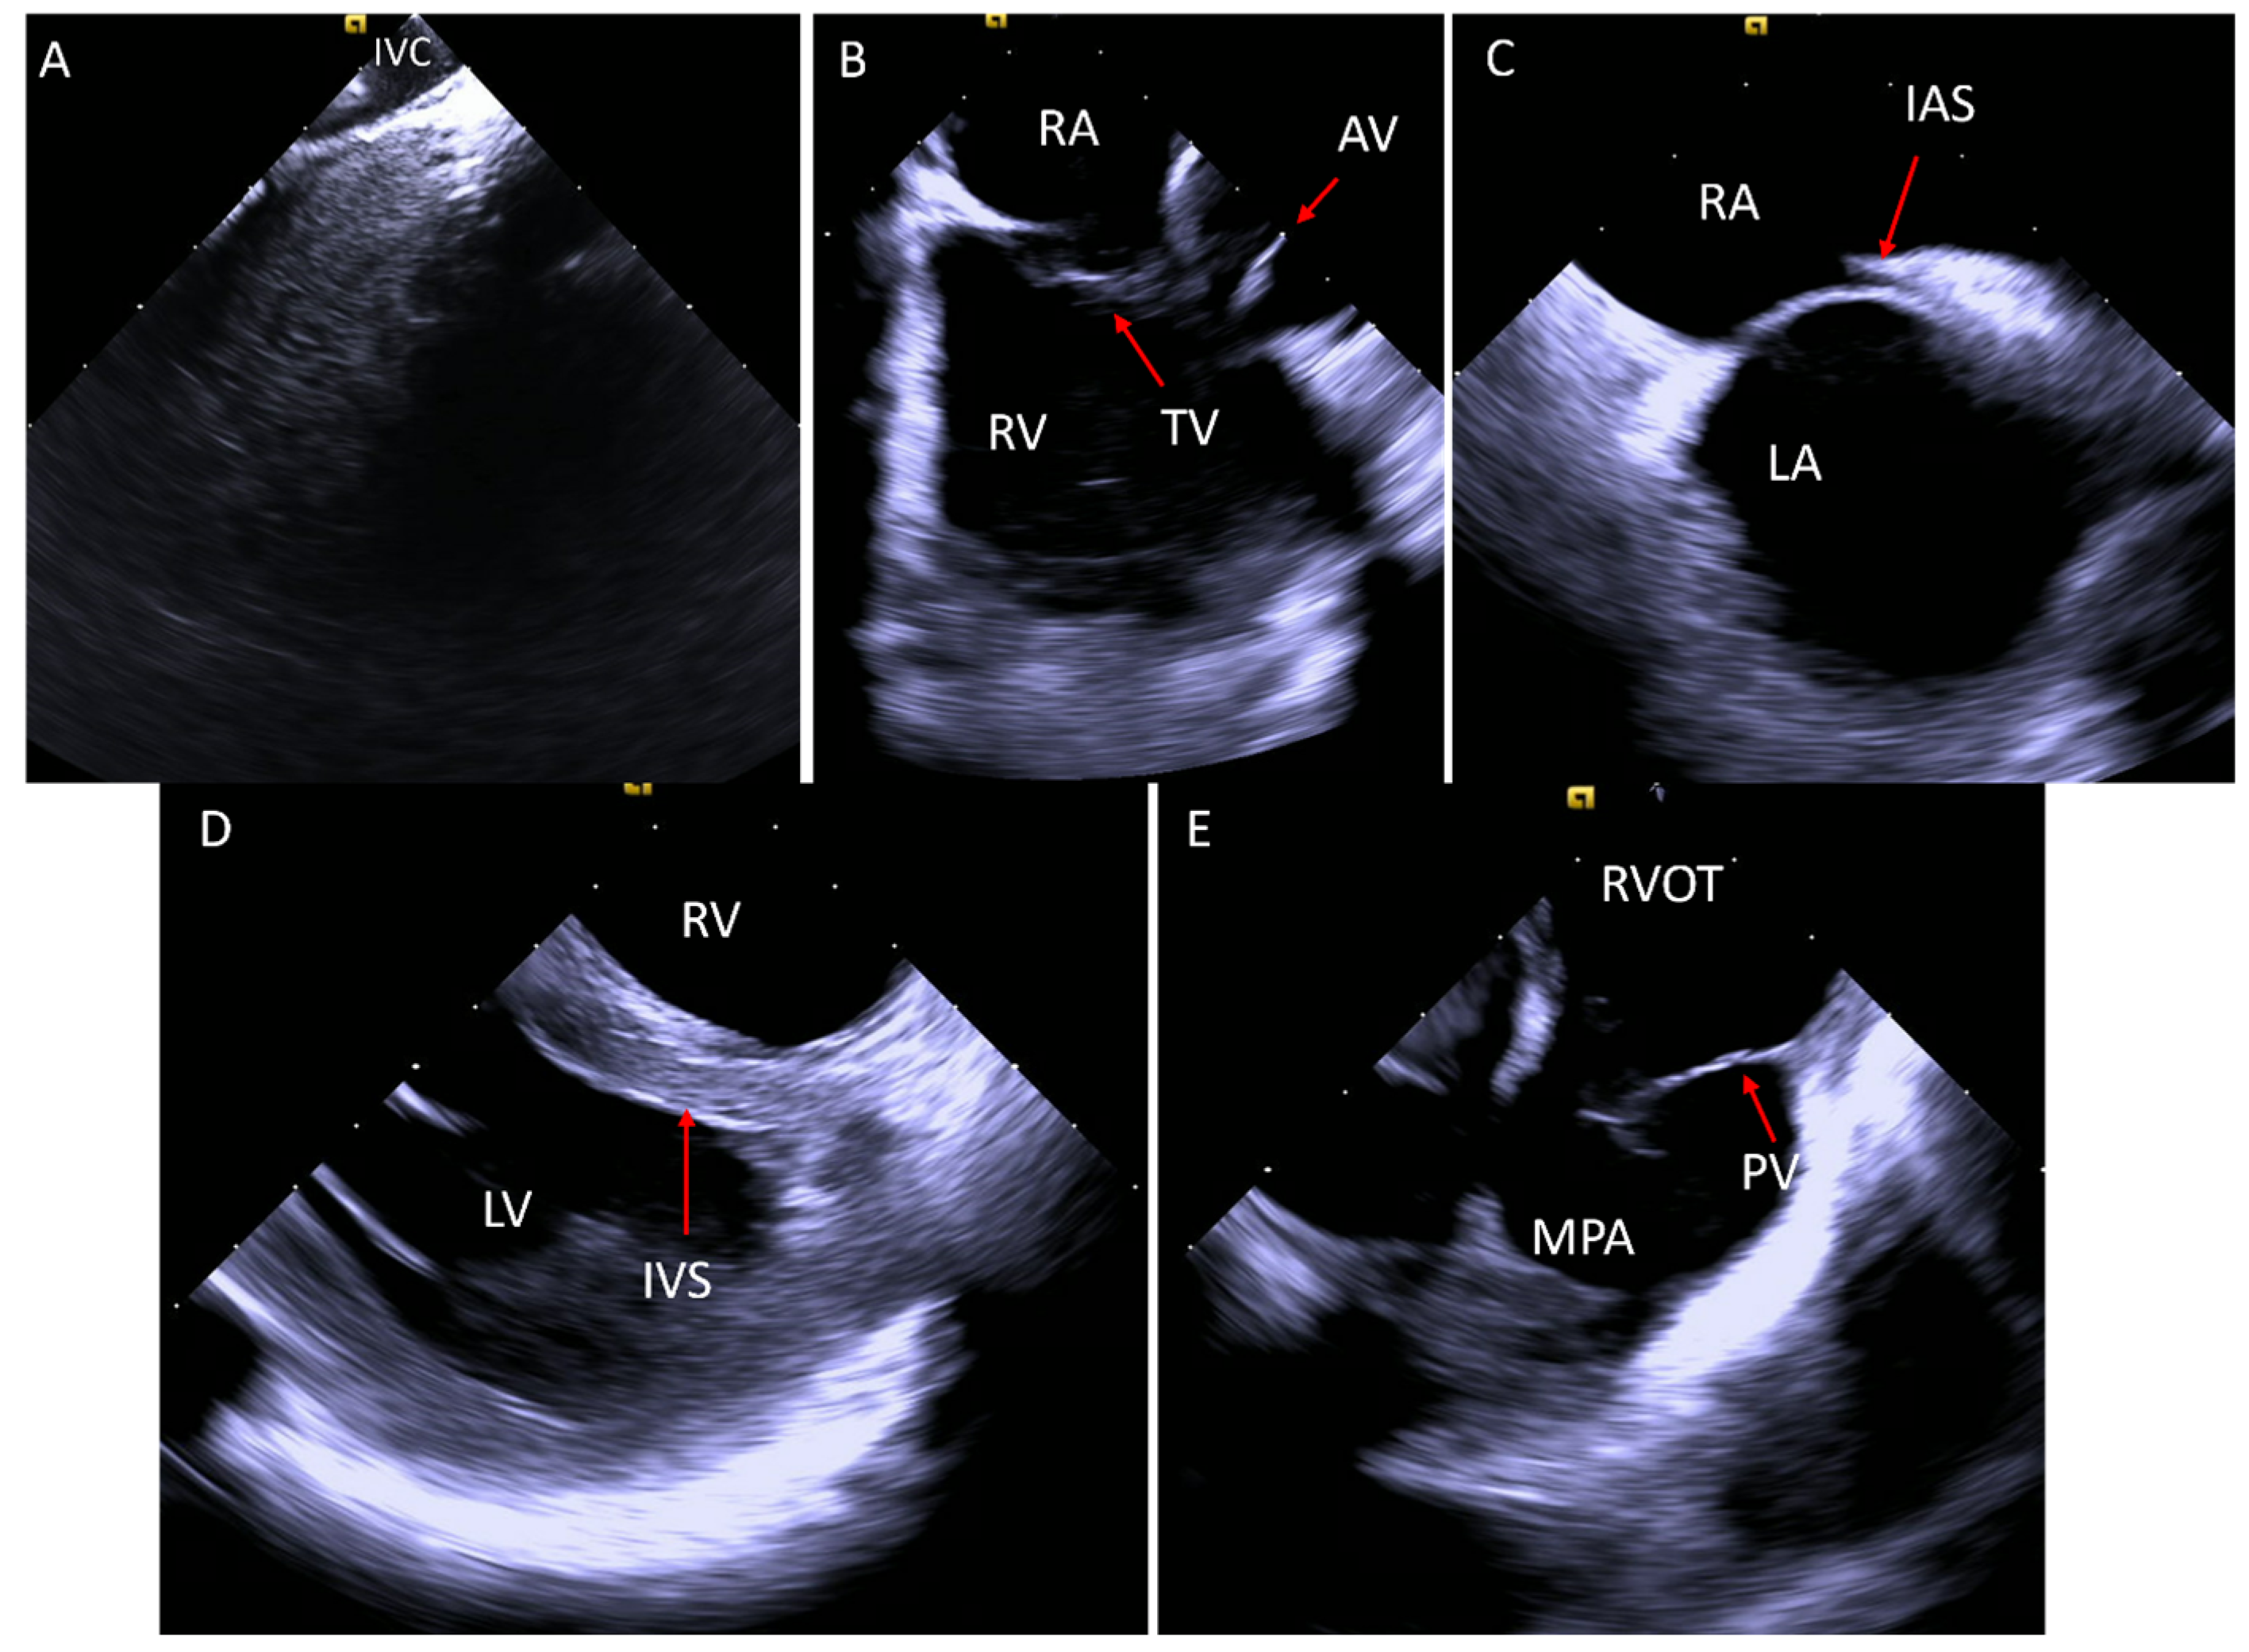

2. Acquiring Baseline Images